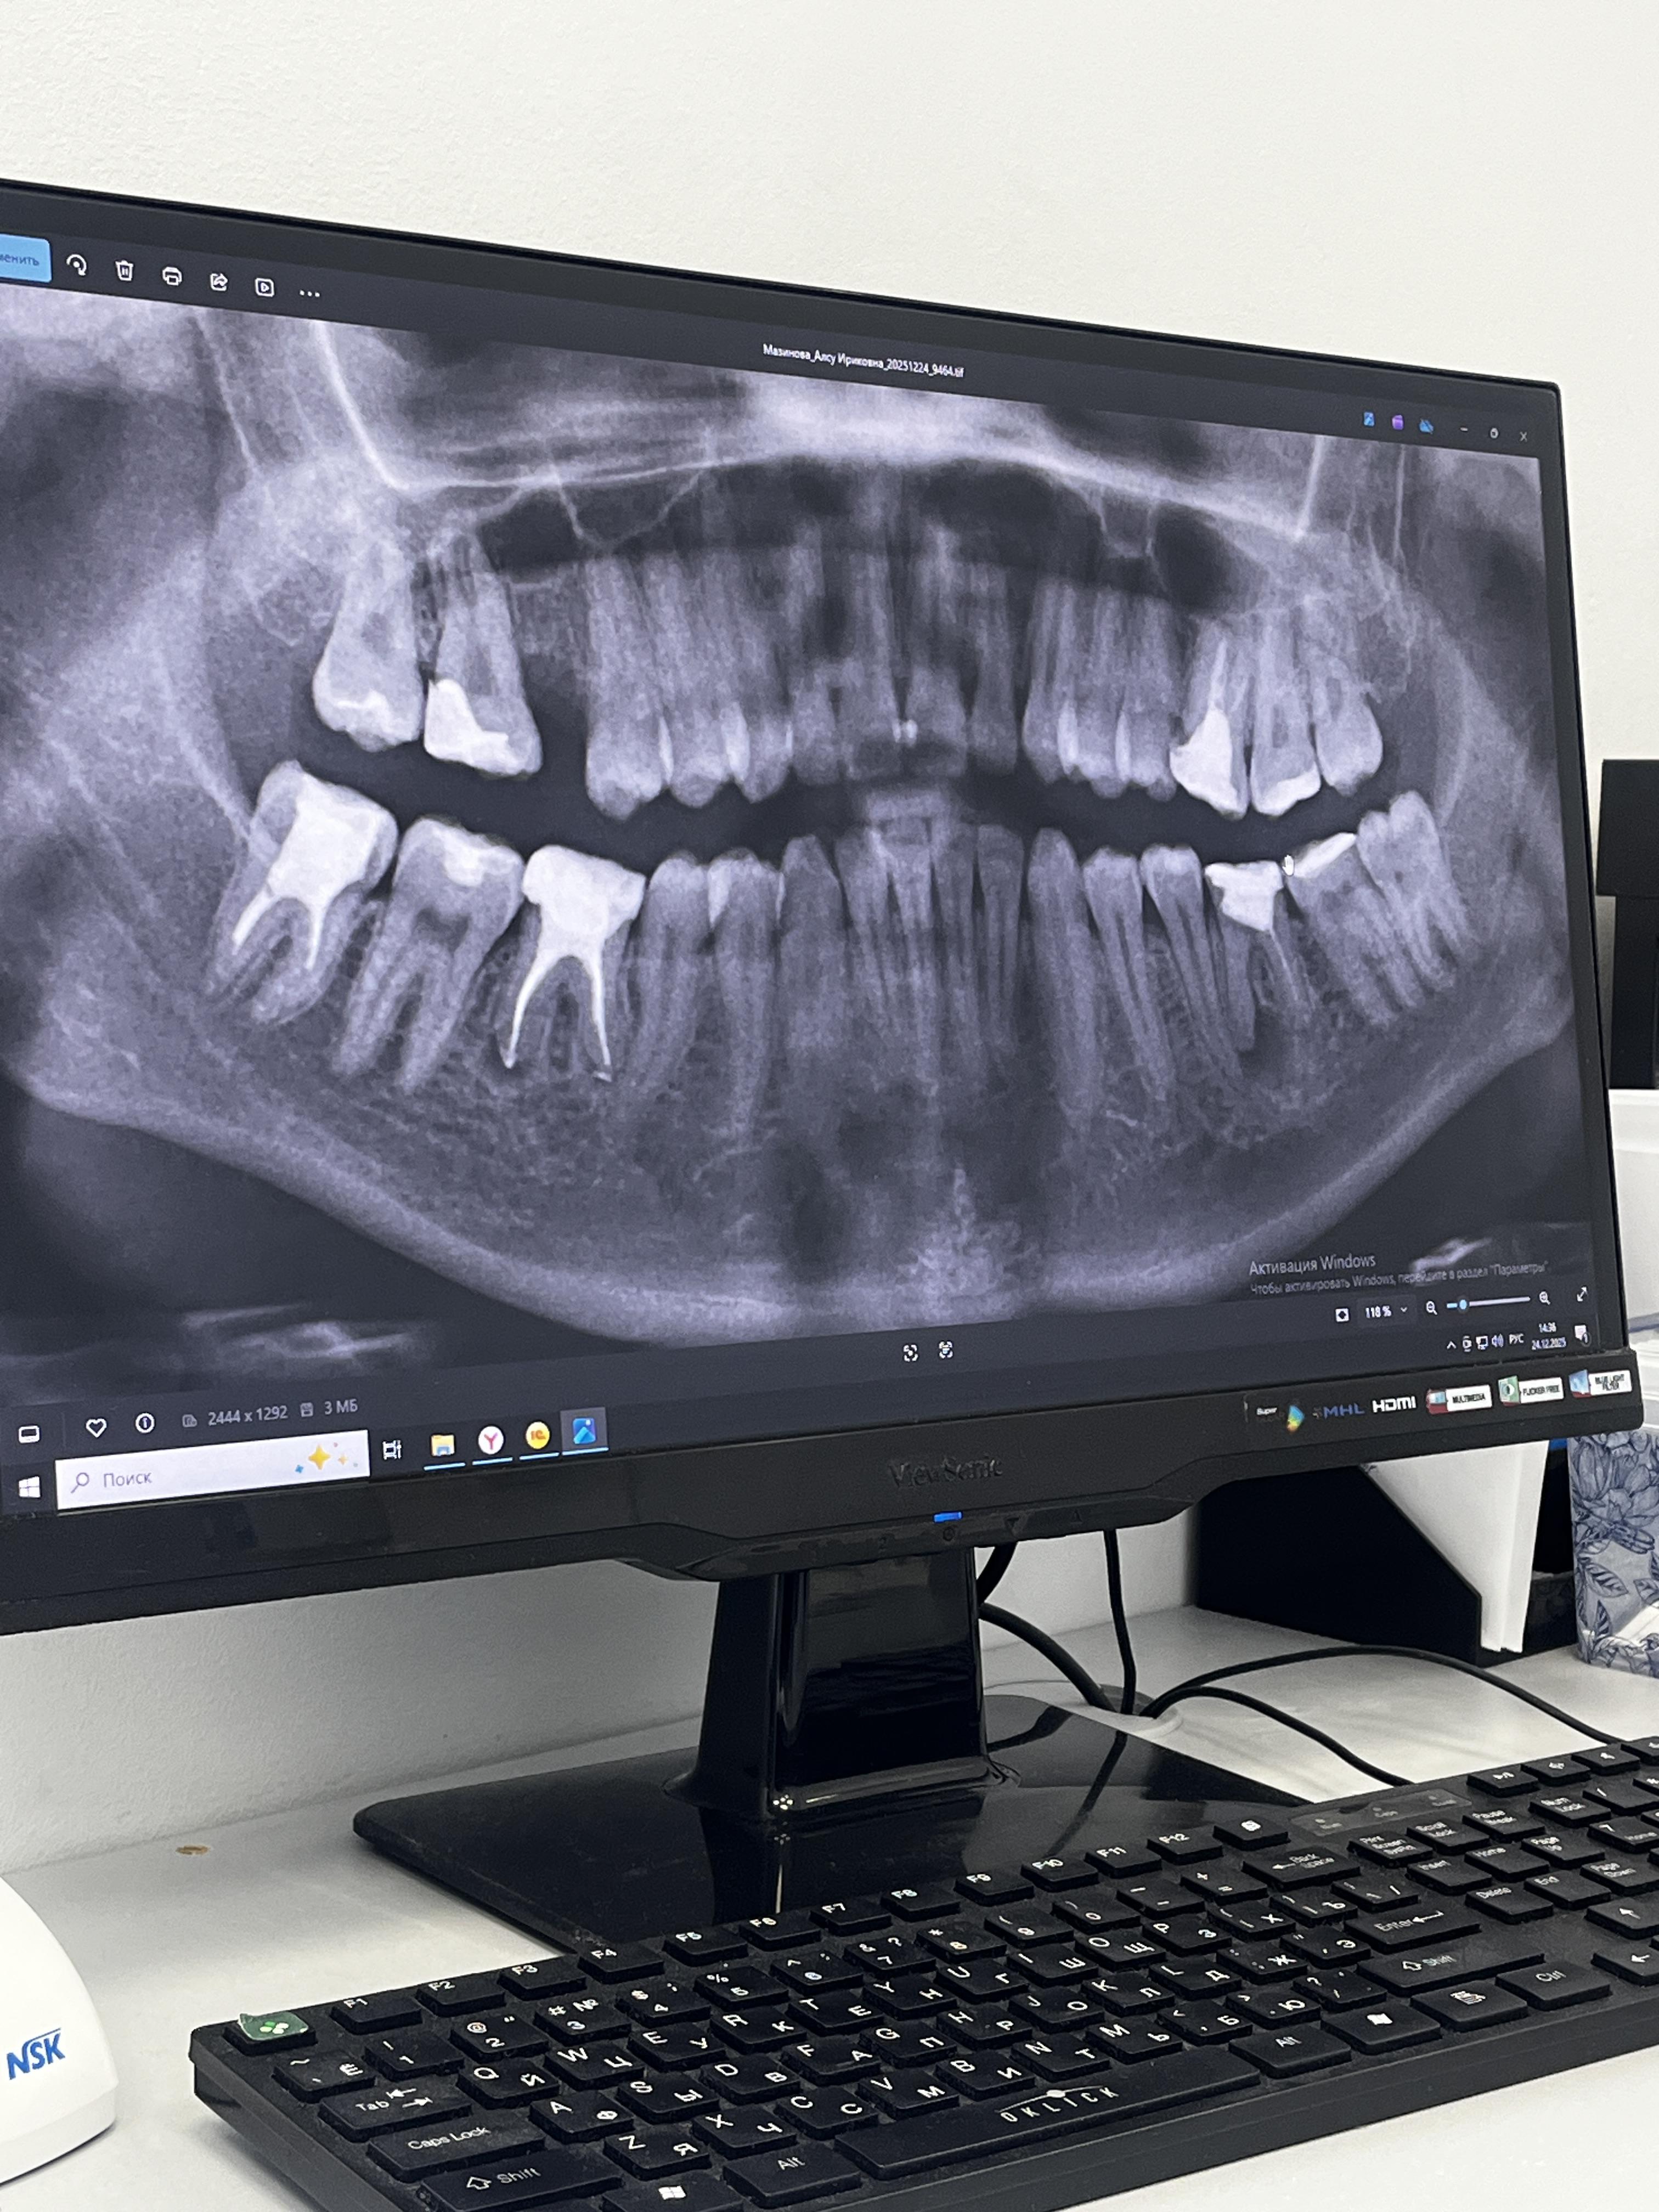

Обращаюсь с такой проблем, сходила в одну стоматологию, прописали план лечения такой: удалить оставшиеся шестерки, нижнюю восьмерку справа и поставить брекет-систему.

Пошла в другую стоматологию, сказали удалить все шестерки и все восьмерки, потом вставить импланты и уже потом лечить брекетами.